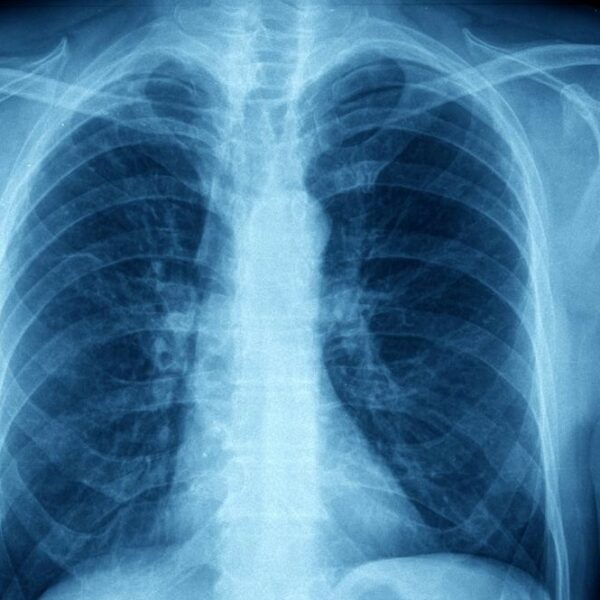

Asthma takes place in two forms; acute and chronic. Acute asthma, known as an asthma attack is an episodic event that occurs due to an asthma trigger. Chronic asthma develops due to the changes that occur from prolonged inflammation over time.

When a patient comes into contact with an asthma trigger, a chain reaction of events occur that leads to an asthma “attack.” The exposure to the trigger will cause the muscles that surround the airways to “clamp down” or contract, thus narrowing the spaces for air to travel through.

It is believed that patients always have some degree of inflammation in the lungs that make them more sensitive triggers. Chronic inflammation over time can lead to changes in the structures of the lungs and increased mucous production. Proper control of asthma can limit these effects.